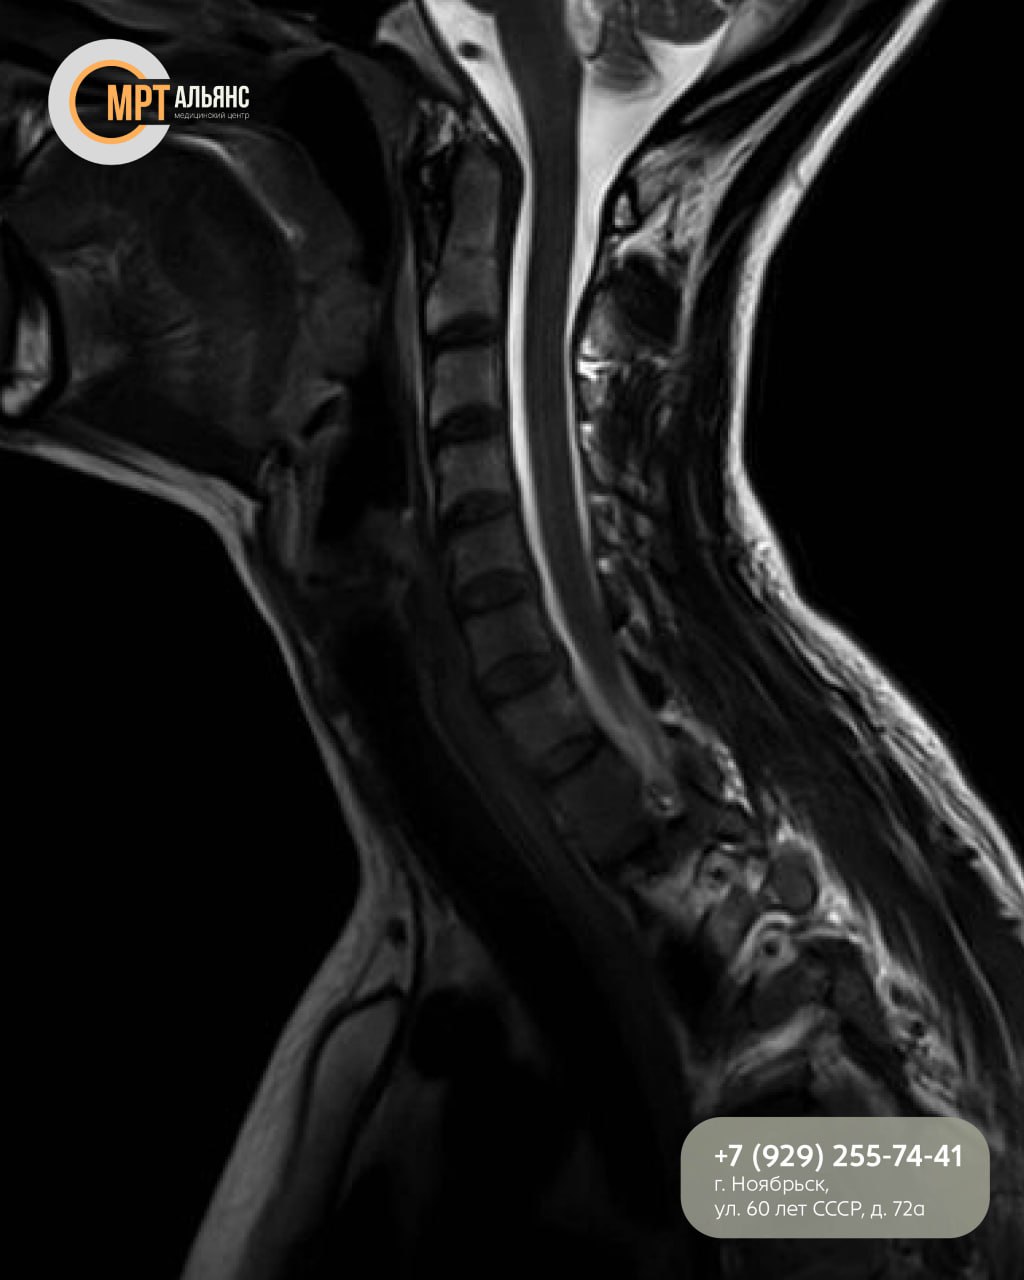

МРТ шейного отдела детально показывает:

· Позвонки и межпозвонковые диски

· Позвоночный канал и спинной мозг

· Нервные корешки и межпозвонковые суставы

· Состояние мягких тканей

Исследование позволяет точно диагностировать протрузии, грыжи, остеохондроз и последствия травм!